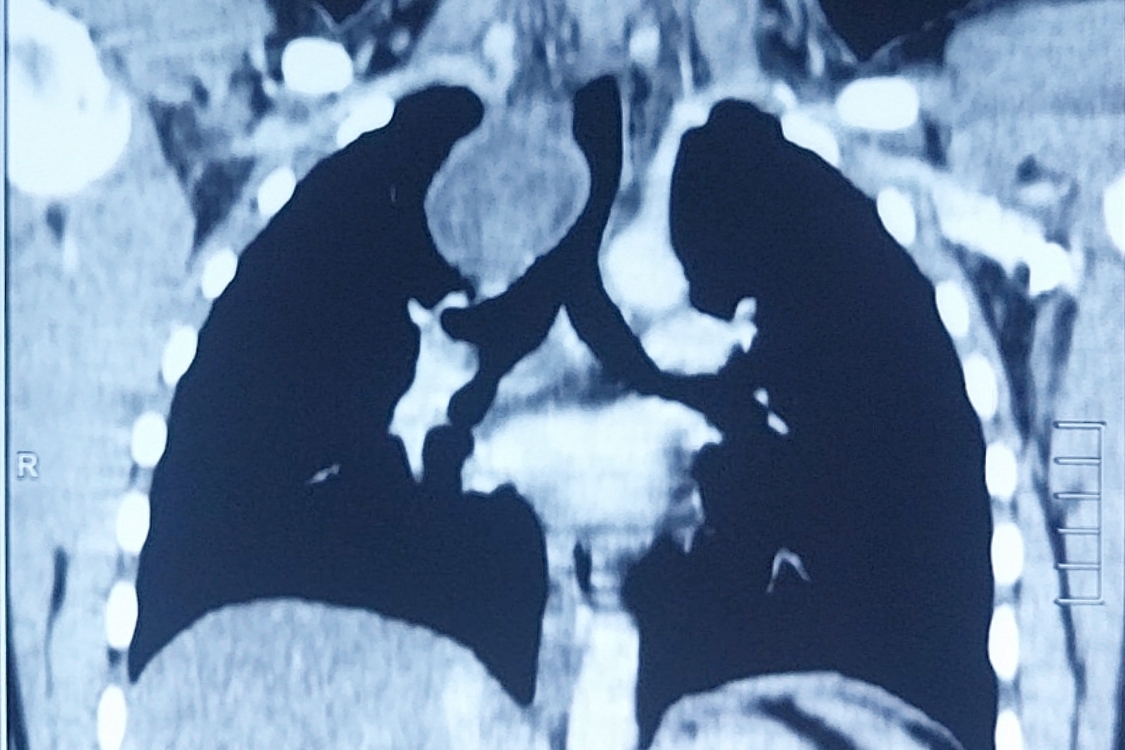

A 16-year-old boy presented with chest pain for the previous seven days that was more on the right side, gradual in onset, dull in character, intermittent, and radiating to the back. It was aggravated on exertion and was relieved with rest. The pain was associated with shortness of breath. The patient also complained of dysphagia, which was occasional and progressive. There was no history of cough or recent chest infection. General physical and systemic examinations were unremarkable. He had a low-grade fever with a hemoglobin of 13.5 g/dl, white cell count of 12.4/dL, and ESR of 52. Other routine lab investigations were within normal limits. His chest x-ray showed a right mediastinal round opacity on the right side of the carina. On his CECT scan Chest, the authors found a well-marginated nonenhancing thick fluid-attenuating lesion centered at the right paratracheal location in the middle and posterior mediastinum on the right side that was pressing on the esophagus and trachea.

Figure 2. CECT of the chest showing a round homogenous cystic lesion in the right paratracheal region pressing on the esophagus and trachea.